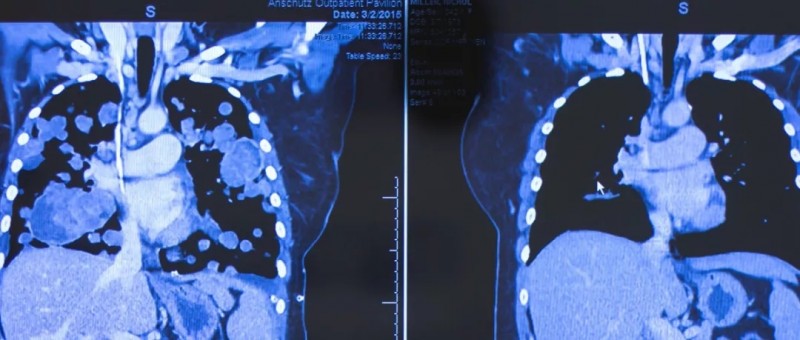

这个拿着手机拍照的女人叫Nichol Miller,她正不可置信的看着最新的CT结果,赶紧拍下来分享给自己的丈夫。因为就在几个月前,坐在轮椅上的她,肿瘤已经填满了双肺的90%,连呼吸都困难,需要一直吸氧才能维持,医生都已经宣布她的生命即将走到尽头。而正是拉罗替尼完全改变了她的生死!